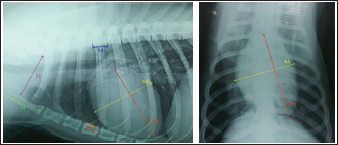

Objective methods for assessment of blood vessels relevant to the HWD included several measurements (Fig. 2A and B) and calculations. The diameters of blood vessels relevant for the HWD (RCrLA, RCaLA, and VCC) were first measured and expressed in absolute values (mm). The diameters of the vessels were measured perpendicular to their LA. Relative measurements of the relevant blood vessels were expressed as ratios to the T4 (for all three blood vessels), and to the 4.r (for the RCrLA and VCC), to the 9.r (for the RCaLA), and to the Ao (for the VCC). The T4 was measured as described in modified VHS methods. The measurement of the 4.r was done on its proximal part as the smallest diameter. The measurement of the 9.r was measured at its intersection with the RCaLA. The Ao was measured at the descending part (Herrtage and Denis, 1997; Lehmkuhl et al., 1997; Arya et al., 2021).

Fig. 2. A and B. Measurements of blood vessels relevant to the HWD in LL (A) and DV (B) radiographs: RCrLA – the width (mm) of the RCrLA, VCC – the width (mm) of the VCC, Ao – the width (mm) of the Ao, T4 – the length (mm) of the body and caudal disc of the T4 vertebra, 4.r – the width (mm) of the 4.r, RCaLA – the width (mm) of the right caudal lobar artery, 9.r – the width (mm) of the ninth rib.